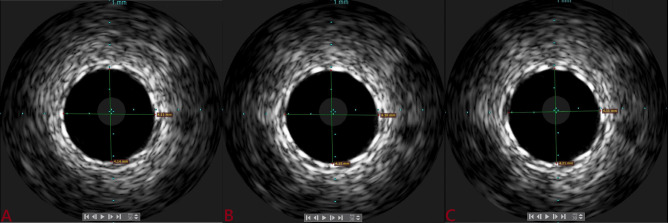

Background: Intravascular ultrasound (IVUS)-guided percutaneous coronary intervention (PCI) is useful for stent optimization. Outcomes of the ultrathin Supralimus Tetriflex stent (Sahajanand Medical Technologies Pvt. Ltd., India) using IVUS were evaluated among patients with short (≤ 20 mm) versus long lesions (≥ 20 mm).

Methods: A total of 207 patients underwent PCI, and IVUS was performed post-deployment. The primary outcome was optimal stent deployment, defined as (a) mean surface area (MSA) >5.0 mm²; (b) plaque burden <50%; (c) complete apposition; and (d) no edge dissection. Secondary outcomes were target lesion failure (TLF)-a composite of cardiac death, target vessel myocardial infarction (TVMI), and target lesion revascularization (TLR)-stent thrombosis, and major adverse cardiovascular events (MACE; a composite of death, MI, stent thrombosis, and repeat revascularization).

Results: Suboptimal deployment was significantly more frequent among patients with longer lesions (30.1% vs. 23.3%; p=0.03) due to higher rates of malapposition (17.3% vs. 10.6%) and MSA <5 mm² (9.6% vs. 7.7%). Following post-dilatation, suboptimal deployment was observed in 7.6% and 5.8% of patients, respectively. Residual plaque burden was 4.5% and 5.7%, respectively. The MSA in both groups was 6.3 mm² and 6.5 mm². Minimum and mean stent expansions were 82.1% versus 81.7% and 106.3% versus 109.8%, respectively, with no significant differences. TLF and stent thrombosis were observed in 0.9% versus 0.9% and 2.9% versus 3.8% of patients, respectively, with no significant differences. However, MACE was significantly higher (10.5% vs. 8.7%; p=0.05) among patients with longer lesions.

Conclusion: Supralimus Tetriflex stent has very good optimal deployment based on angiogram and becomes better with IVUS imaging, making it safe among long lesions (≥ 20mm).